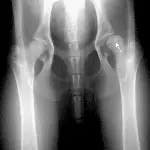

Figure 3A. This series represents an example of a probable fracture that cannot be seen on routine radiographs but that produces secondary signs that can be seen. Slight thickening of the caudal cortex of the tibia (arrow) is present in a dog with left hind limb lameness. The dog is an active, 3-yearold, castrated male black Labrador retriever having lameness for several months but with no prior history of lameness.

Figure 3B. Lameness was persistent, and cortical thickness progressed (arrow) over a 4-month period. Panosteitis might be considered in the differential diagnosis because of the several areas of uptake, although panosteitis does not typically start as a focal unicortical thickening of the bone in a 3-year-old dog.

Figure 3C. A bone scan was positive in the shaft of the tibia and was suggestive of a hairline stress fracture.

Figure 3D. Several small holes were drilled in the affected cortex (osteostixis) to encourage neovascularization and bone healing. The lameness resolved after treatment.